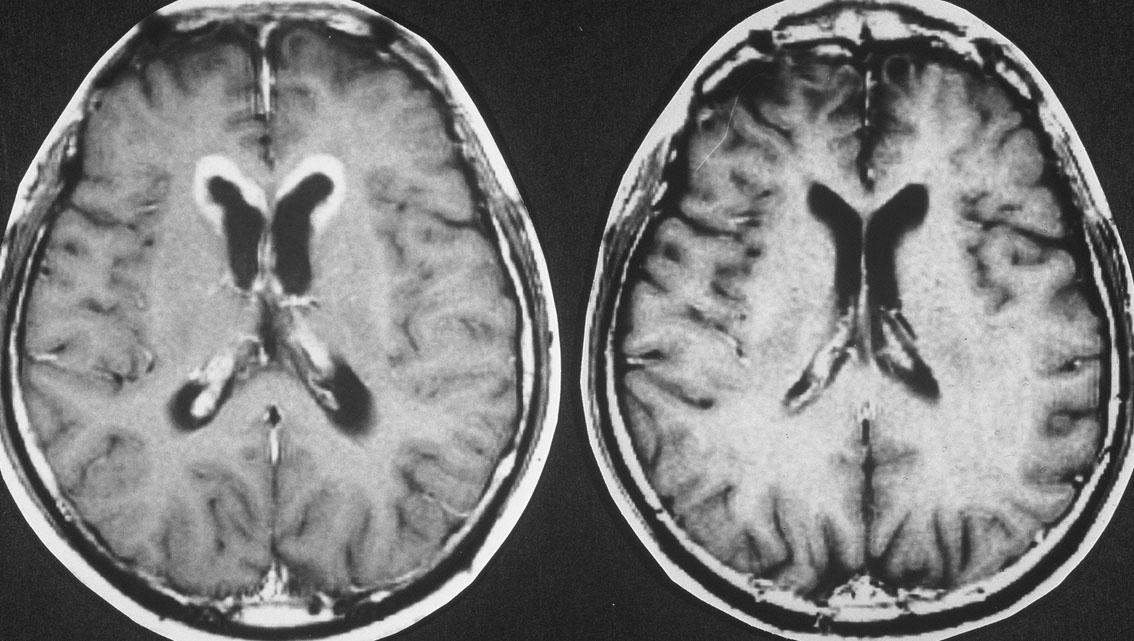

11歳(1977年)で発症して放射線治療を受け,21歳(1987年)で再発しました。側脳室の前角にガドリニウム増強される典型的なgerminomaの再発像がみれます。脳表にも脊髄にも髄液播種はありませんでした。

CDDP/VP-16化学療法で腫瘍は消失し,放射線治療を加えました。

2度目の再発です。側脳室の壁に再発したので,また化学療法をしましたら,右の画像のようにきれいに消えました。この時点でも髄液吸収障害性水頭症にも閉塞性水頭症にもなっていません。

3度目の再発です。また脳室の壁から再発しました。化学療法で腫瘍はまた消失しました。その後も維持化学療法を行ったのですが,脳室内再発が止められず,第4脳室底部の腫瘍が延髄に浸潤して死亡しました。

最後まで水頭症はありません。